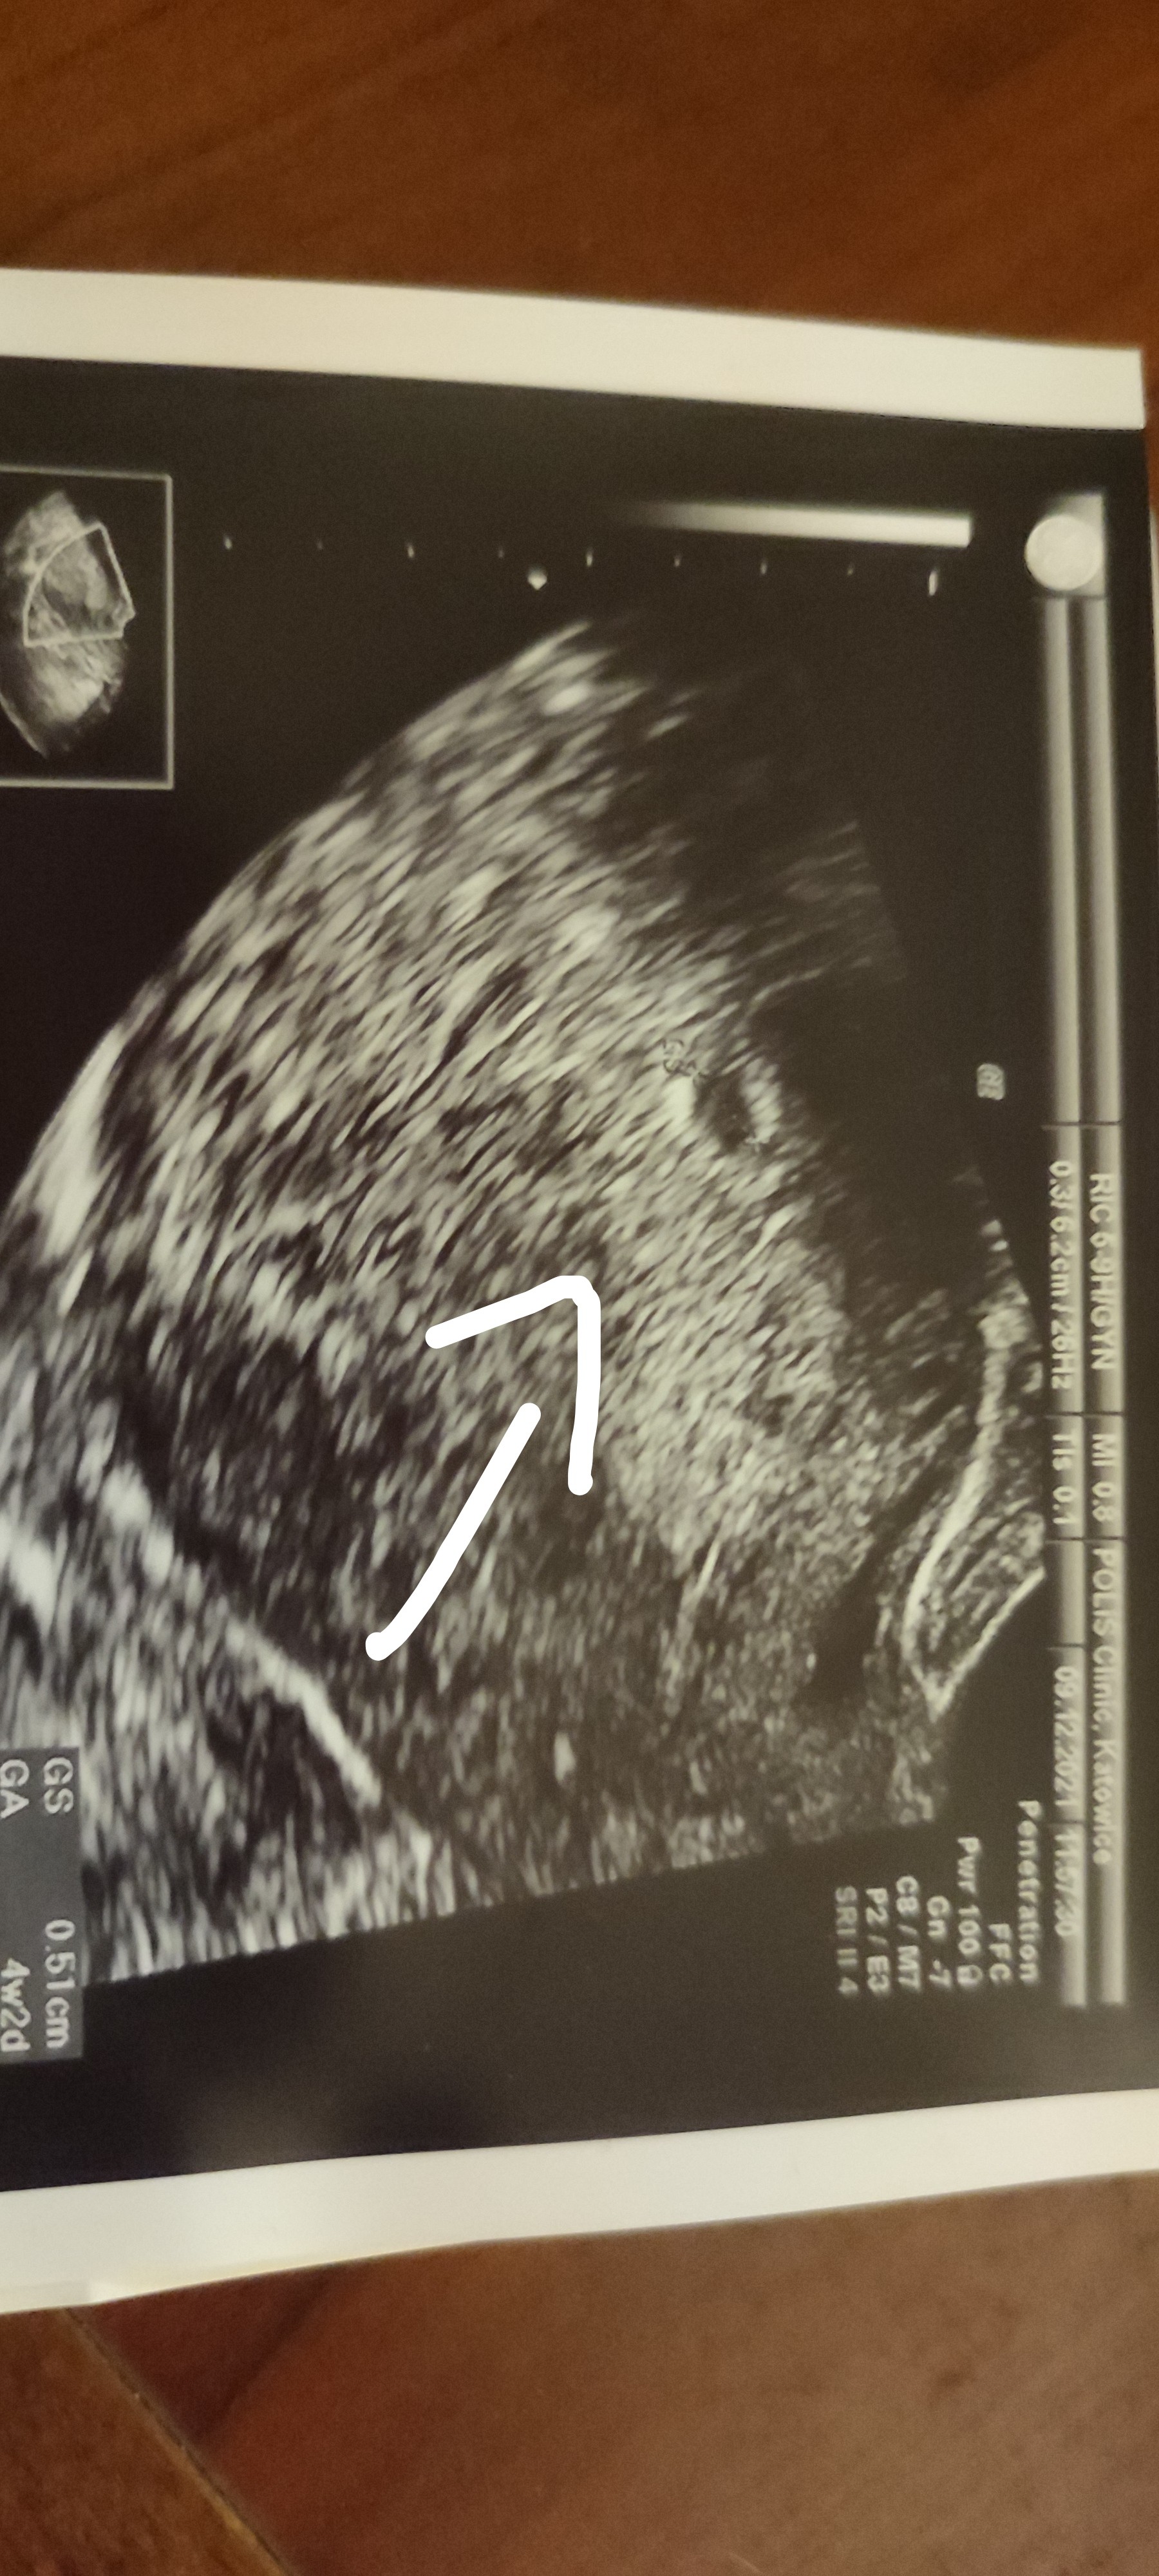

Niska Beta HCG

Jest pęcherzyk ♥️ za 2 tygodnie kolejna wizyta 🥰. Lekarz mówi, że wszystko w porządku 🤗

Załączniki

• IMG_20211209_174650.jpg

1,2 MB · Wyświetleń: 174